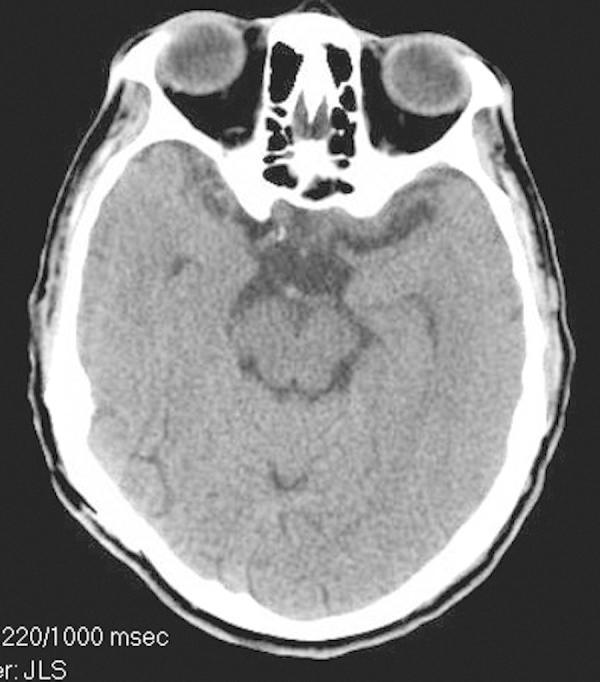

The Mycobacterium avium-intracellulare complex (MAC) is an uncommon cause of brain abscesses even in patients with acquired immunodeficiency syndrome (AIDS). We present a case of a multiple MAC brain abscesses, confirmed by brain biopsy and culture, in a patient with AIDS. The patient's initial symptoms were weakness, confusion and headaches. The patient was initially treated for toxoplasmosis and pyogenic bacterial brain abscesses with no resolution. Following treatment for MAC the patient's abscesses resolved.

鸟分枝杆菌-胞内分枝杆菌复合体(MAC)即使在获得性免疫缺陷综合征(AIDS)患者中,也是脑脓肿的不常见病因。我们报告一例经脑活检和培养确诊为多发性MAC脑脓肿的AIDS患者。患者最初的症状是虚弱、意识模糊和头痛。患者最初接受了弓形虫病和化脓性细菌性脑脓肿的治疗,但病情未缓解。针对MAC进行治疗后,患者的脓肿消退。